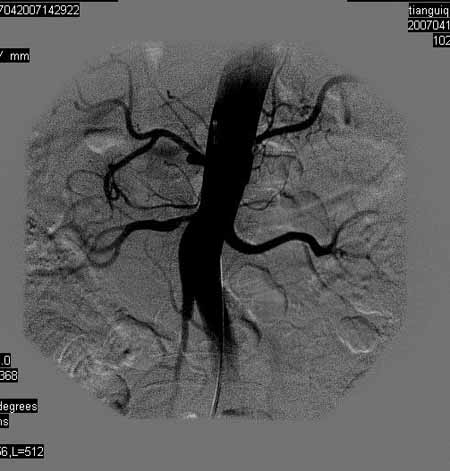

标题: DSA0093:脑血管造影

女,63岁,左侧额、枕叶脑梗塞。

右肾动脉及左颈内动脉起始部狭窄(考虑动脉硬化引起的),大脑中动脉分支减少.